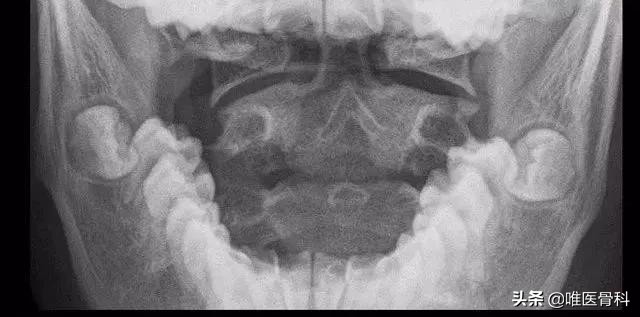

可能需要拍个颈椎侧位片和开口位片,来排除寰、枢椎骨折、脱位和半脱位。侧位像上看颈椎序列曲度如何,有没有强直、反屈、滑脱,看看环、枢间隙,正常成人环枢间隙不超过3mm,儿童不超过5mm,超过了说明环枢椎间不稳定,可能还得加拍颈椎过屈、过伸位。

开口位主要是看枢椎齿状突在没在环椎椎弓根影(侧块)中间,如不对称可能为枢椎齿状突骨折、环枢脱位、半脱位。孩子拍片不配合时也可行上颈椎CT平扫检查确诊。